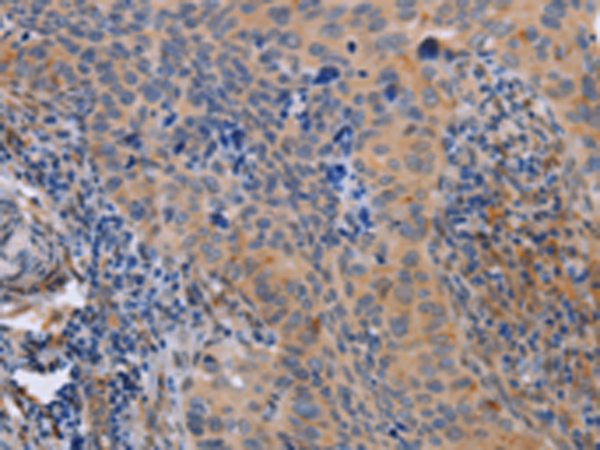

分类: 科研抗体货号: P07954别名: MAY1; PKCD; nPKC-delta应用: WB,IHC反应种属: Human, Mouse, Rat

分类: 科研抗体货号: P07952别名: BARK2; ADRBK2应用: IHC反应种属: Human, Rat

分类: 科研抗体货号: P07970别名: IDH; IDP; IDCD; IDPC; PICD应用: WB,IHC反应种属: Human, Mouse, Rat

分类: 科研抗体货号: P07986别名: HK; HKD; HKI; HXK1; RP79; HMSNR; HK1-ta; HK1-tb; HK1-tc; hexokinase; HKII; HXK2应用: WB,IHC反应种属: Human, Mouse, Rat

分类: 科研抗体货号: P07969别名:应用: IHC反应种属: Human, Mouse

分类: 科研抗体货号: P07978别名:应用: WB,IHC反应种属: Human

分类: 科研抗体货号: P07985别名: HXK3; HKIII应用: IHC反应种属: Human, Mouse, Rat

分类: 科研抗体货号: P07968别名:应用: IHC反应种属: Human, Mouse, Rat

分类: 科研抗体货号: P07977别名: LZK; MLK; MEKK13应用: IHC反应种属: Human, Mouse